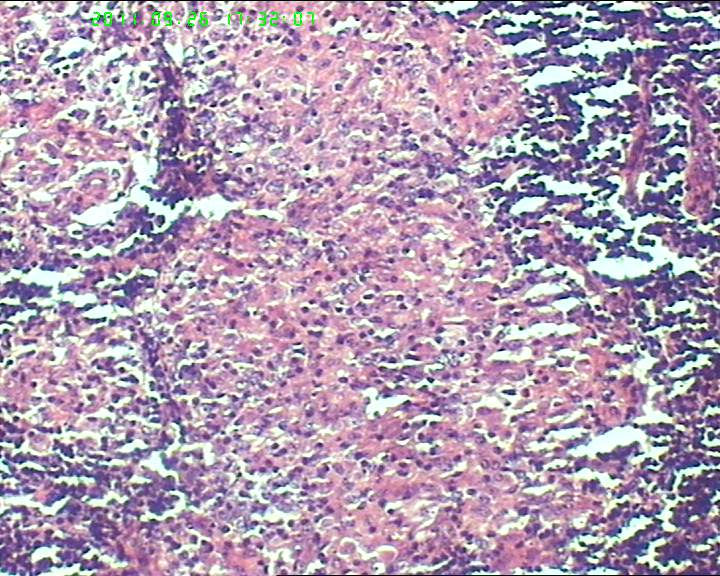

21岁女性左侧颌下淋巴结,该诊断什么?

灰白不整形肿物一个,大小3.5*2.5*2cm,包膜完整。

21岁女性左侧颌下淋巴结,该诊断什么?图3

慢性肉芽肿性炎症,形态学倾向结节病,但是作为病理工作者对于这样的病例,再结合咋们国情,还是建议临床除外增殖性结核后再考虑结节病。

肉芽肿性炎症,倾向结节病。

最好做做抗酸染色、网状纤维染色和PAS后看看再定。